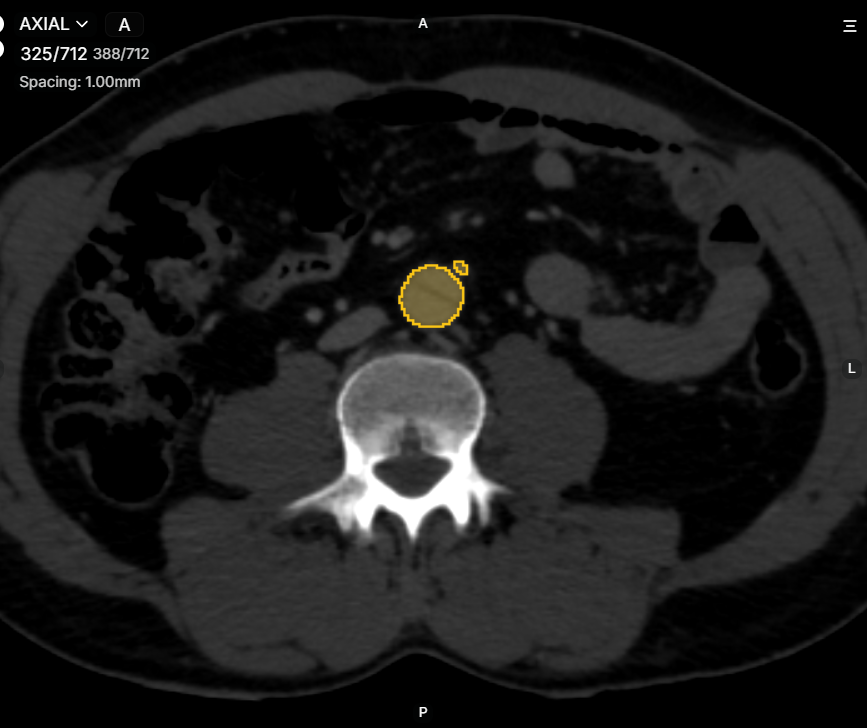

Our cutting-edge segmentation services utilized advanced algorithm platforms to accurately identify and delineate anatomical structures in medical images, which were crucial for effective diagnosis and treatment planning. These technologies enabled us to achieve high levels of accuracy in segmenting anatomical structures and pathological regions within medical images. The applications of medical image segmentation were vast, ranging from Aneurysm detection and organ delineation to the assessment of disease progression. By providing precise segmentation, we empowered healthcare Professionals to make informed decisions regarding diagnosis and treatment planning. We completed many segmentations with accuracy and quality across various parts of the body and different imaging modalities (Such as CT, MRI, DSA, etc.) covering a range of pathologies (Such as Occlusion, Infarct, Dissection, etc.) in multiple types of imaging (CTA, NCCT, MRA, etc.).

- CT Scan Segmentation for detecting lung diseases, tumors, and fractures.

- AI Medical Image Analysis is used in detecting lung nodules in CT Scan Segmentation, aiding early lung cancer diagnosis.

Surgeons rely on Medical Image Segmentation to plan procedures with precision. AI-generated 3D models assist in:

- Visualizing tumors and anatomical structures.

3. Radiation Therapy Optimization

In oncology, Deep Learning for Medical Imaging ensures accurate tumor boundary segmentation for radiation therapy. This minimizes damage to surrounding healthy tissues while targeting cancer cells effectively.